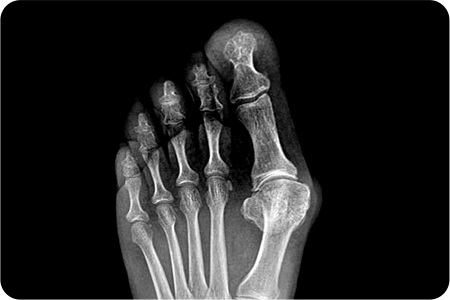

무지외반증 수술 적용사례

1

최소침습

무지외반증 수술

엄지발가락 부위에 약 2~3mm 크기의 작은

구멍을 만들고 특수한 미세 절삭 기구를 사용해

변형된 뼈를 절골하여 올바르게 교정합니다.